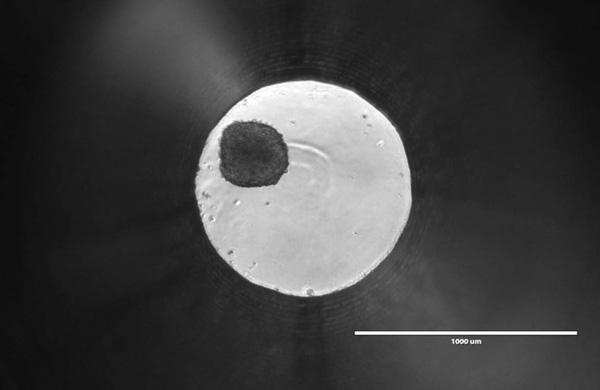

There’s something beautiful about the tiny ball I’m looking at through the microscope. It’s only about 200—250 microns in diameter, smaller than a single grain of salt. As I bump the plate with my finger, the ball rolls around the 1mm well. To me, it may just look like a dark spot within an illuminated circle, but many scientists feel it could represent the future of oncology research and drug discovery.

It’s a Friday afternoon, and I’m staring at a spheroid of roughly 1,000 human liver cells. Promega Research Scientist Mike Valley heard that I was interested in 3-dimensional cell culture models, so he invited me over to his lab in the Research and Development Center to check out the spheroids for myself. Mike is developing a new assay, and with recent trends in cell biology research, he knows it’s crucial to optimize that assay for use with 3D cultures.

3d-cell-1